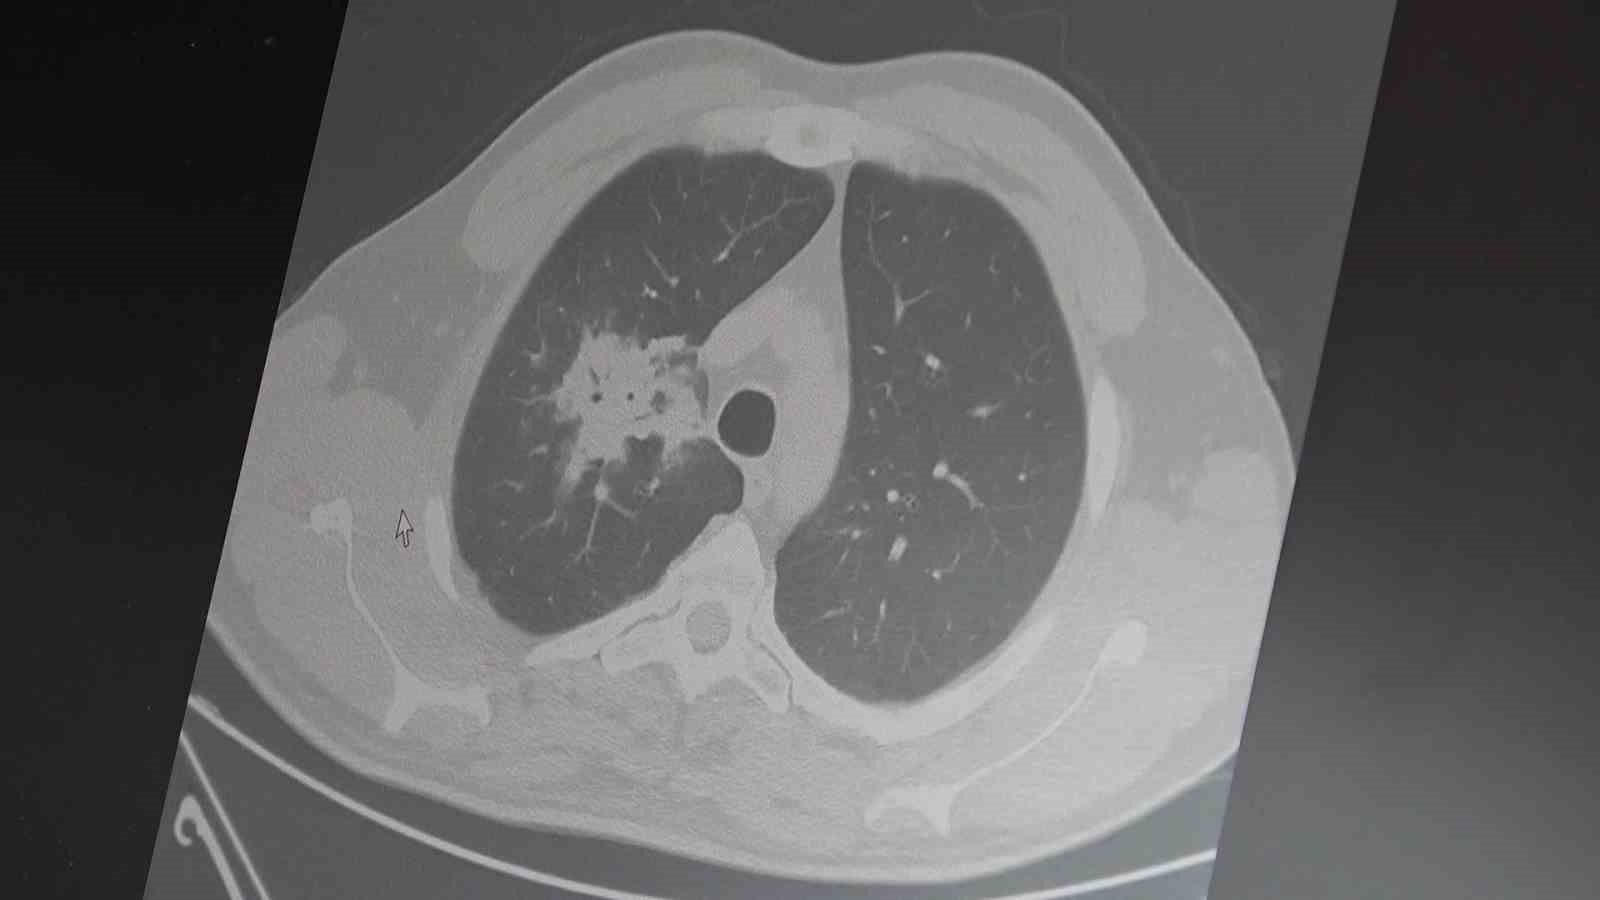

100’den fazla bilimsel çalışmanın incelendiği kapsamlı analizlere dikkat çeken Özkaya, elektronik sigaraların özellikle temas ettiği akciğer ve ağız bölgelerinde kanser riskini artırabileceğine dair güçlü bulgular bulunduğunu belirtti. Uzun vadeli sonuçların henüz tam olarak ortaya çıkmadığını ancak erken uyarı işaretlerinin ciddi olduğunu vurguladı. Araştırmalarda insan, hayvan ve laboratuvar verilerinin birlikte değerlendirildiğini aktaran Özkaya, elektronik sigaraların içerdiği kimyasalların hücre düzeyinde zarara yol açtığının ortaya konulduğunu ifade etti.

Elektronik sigaraların DNA hasarı, oksidatif stres ve kronik iltihaplanma gibi kanser gelişiminde kritik rol oynayan üç temel mekanizmayı tetiklediğini belirten Özkaya, "Bu üç faktörün doğrudan kanser oluşumuna neden olduğunu biliyoruz" şeklinde konuştu.

2024 yılında yayımlanan bir çalışmaya da değinen Özkaya, hem geleneksel sigara hem de elektronik sigara kullanan bireylerde akciğer kanseri riskinin, sadece sigara içenlere göre dört kat daha fazla olduğunun bildirildiğini kaydetti.